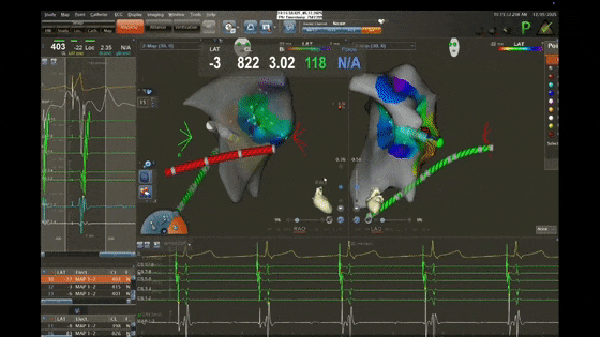

在心血管内科与麻醉科的无缝协作下,全麻成功后,从患儿大腿根部穿刺两针后,送入两根电生理导管到患儿心脏后,连接电生理仪,刺激心脏、诱发心动过速,经过分析,诊断为:左前游离壁隐匿性房室道伴顺向型房室折返性心动过速,即患儿心脏电路系统出现“短路”,位于左心房和左心室之间,导致心动过速,射频消融“短路”,可以治愈此疾病。

术中诱发心动过速,心率达211次/分

三维标测系统图像,标测靶点,黄色箭头